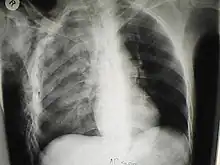

Diagnosis is by physical examination performed by a physician. The diagnosis may be assisted or confirmed by use of medical imaging with either plain X ray or CT scan.